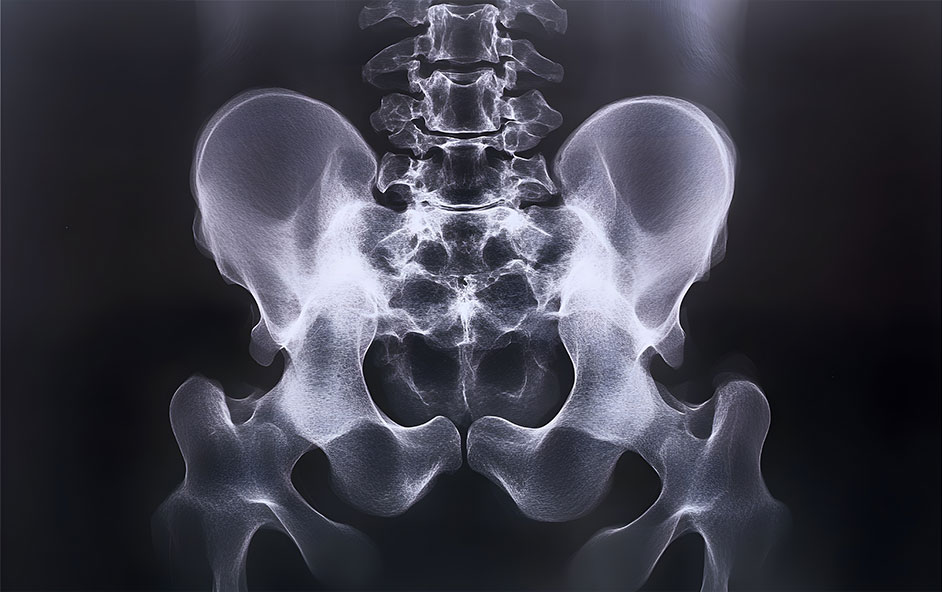

La sacroplastie définition correspond à une procédure qui vise à stabiliser une fracture du sacrum en réalisant une injection de ciment au sein des ailerons sacrés au plus près de la zone fragilisée. Le ciment utilisé est un ciment médical le plus souvent à base de PMMA (polyméthacrylate de méthyle), également appelé sacroplastie PMMA ou sacroplastie ciment acrylique.

On parle souvent de geste de type “cimentoplastie”, car le principe ressemble à celui d’une cimentoplastie vertébrale, mais la technique est adaptée à l’anatomie du sacrum et à la zone fracturée. Il s’agit d’un geste mini-invasif, sans incision chirurgicale classique.

Le geste consiste à introduire une aiguille fine jusqu’à la zone fracturée, sous guidage scanner. Une fois le positionnement confirmé, le médecin procède à l’injection de ciment au niveau du sacrum, généralement un ciment acrylique (PMMA).